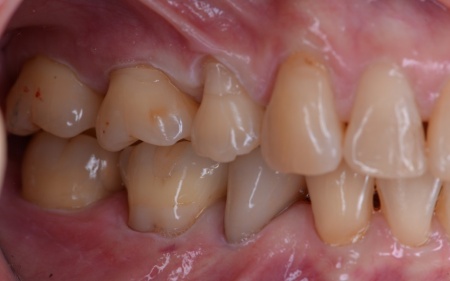

患者様は、歯並びと噛み合わせの根本的な改善を希望されています。

そのため、ワイヤー矯正である程度歯の移動を行ったのち、アライナー矯正(マウスピース矯正)で仕上げを行う矯正治療を提案し、同意いただきました。

その後アライナー矯正に移行し、正しい歯並びになるよう調整を行いました。

最後に、噛み合わせや前歯の隙間が改善されたことを確認して、治療を終了しています。

- 年齢・性別 60代女性

- 治療期間の目安 1年3ヶ月

- 治療費総額の目安 1,100,000円